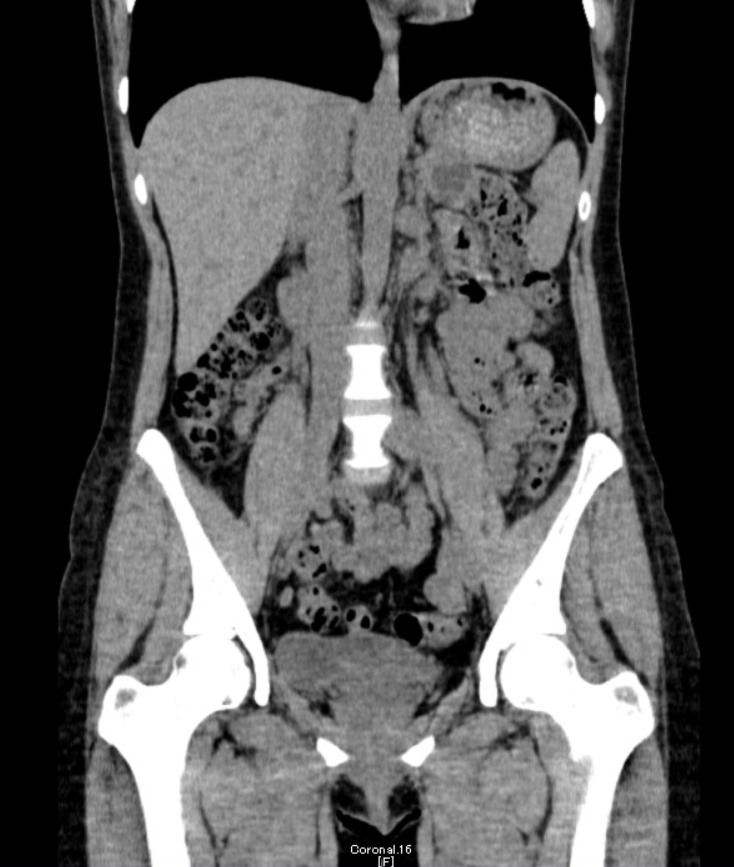

マルチスライスCT

下記など多くの診断ができます。

マルチスライスCT 診断画像

マルチスライスCT 診断画像

- 内頚動静脈・頭蓋内動静脈

- 下肢動静脈

- 尿管・腎臓・膀胱

- 腰椎・骨盤3D

- 腰椎・脊髄

- 骨密度

- 大動脈ステントグラフト挿入後

- COPD・肺気腫

- 大腸がんの肺転移

- 内臓脂肪

- 副鼻腔炎(蓄膿症)

- 硬膜下血腫

- 腎がん

- 多発肝嚢胞

- 膵がん

- 胃がん

- 大腸がん